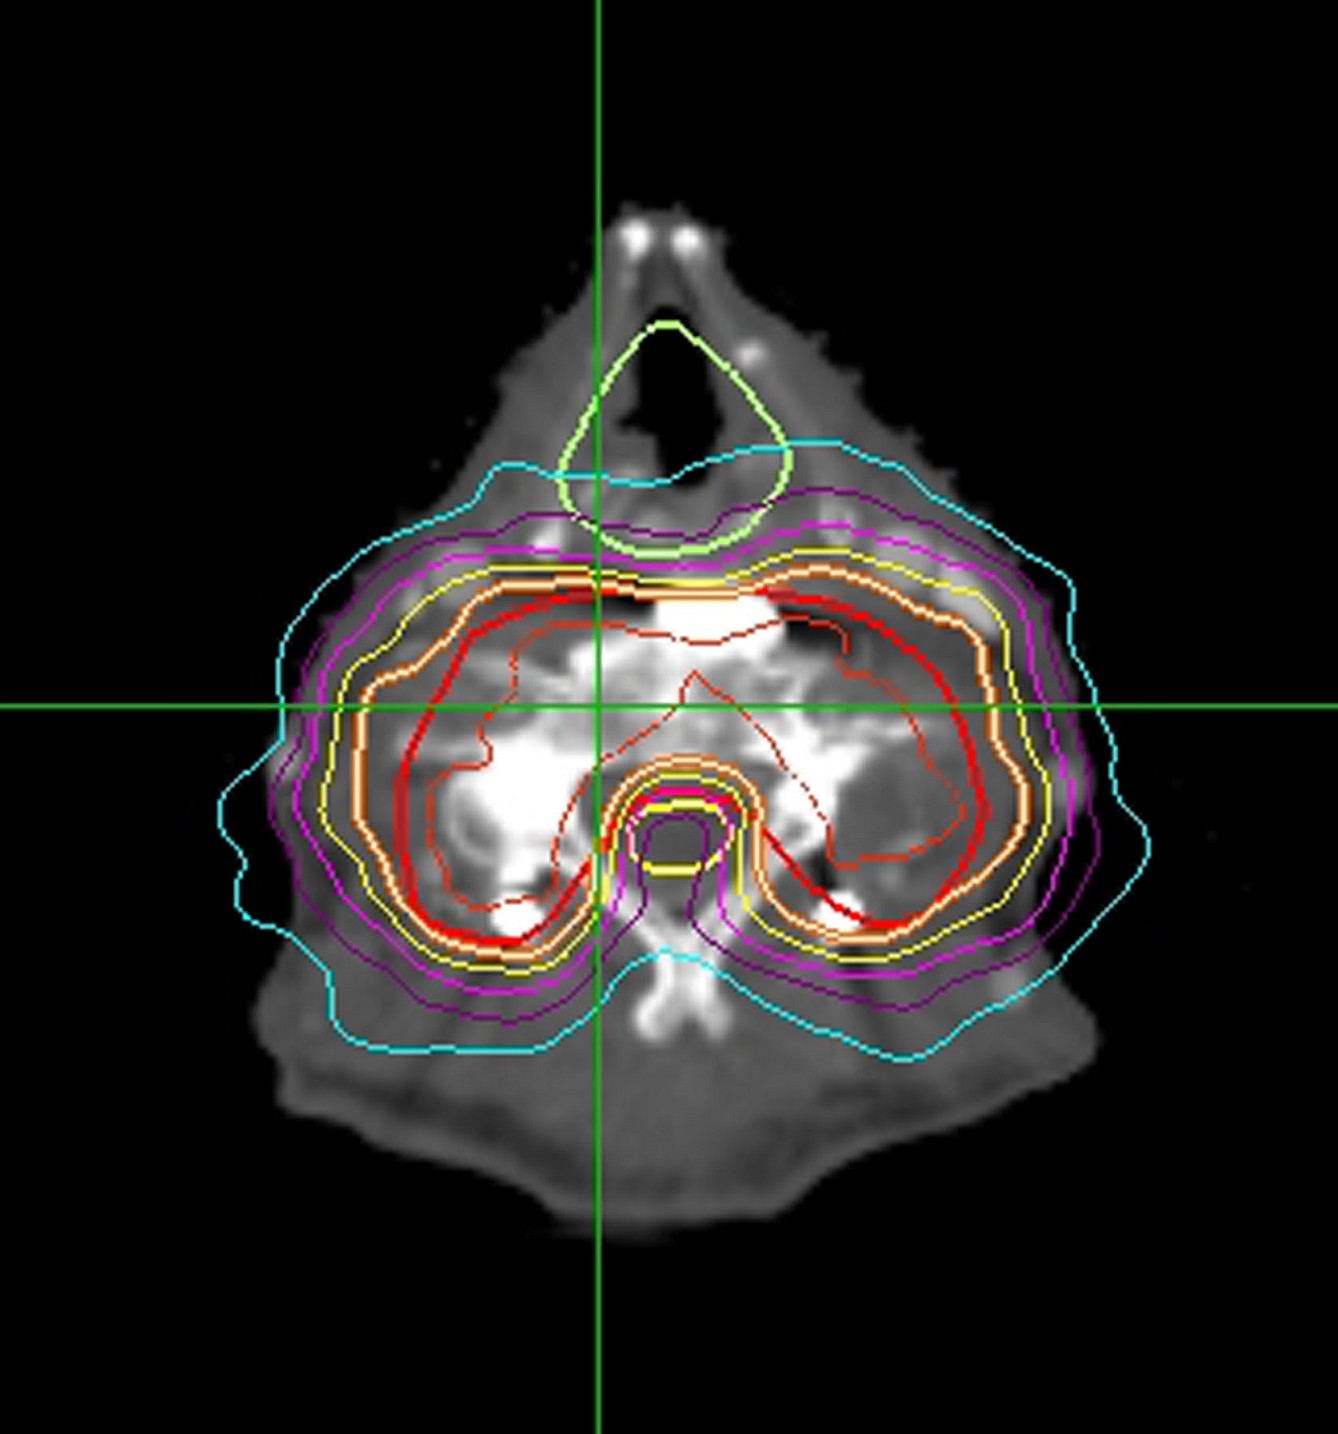

图4 射波刀治疗椎体肿瘤病例